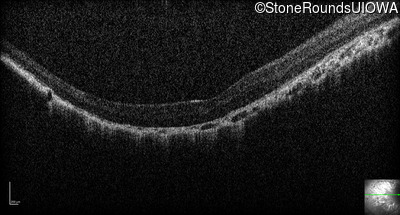

Optical Coherence Tomography - Right - 20/200 +1

Exemplar / OCT Stack